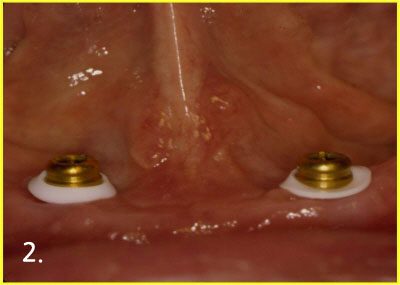

Implant Over-Denture

Placing implant for over-denture

Engaging attachment to implant

Engaging attachment inside denture

After engaging attachment with implant and denture. Now, patient can feel comfortable with denture much more than before